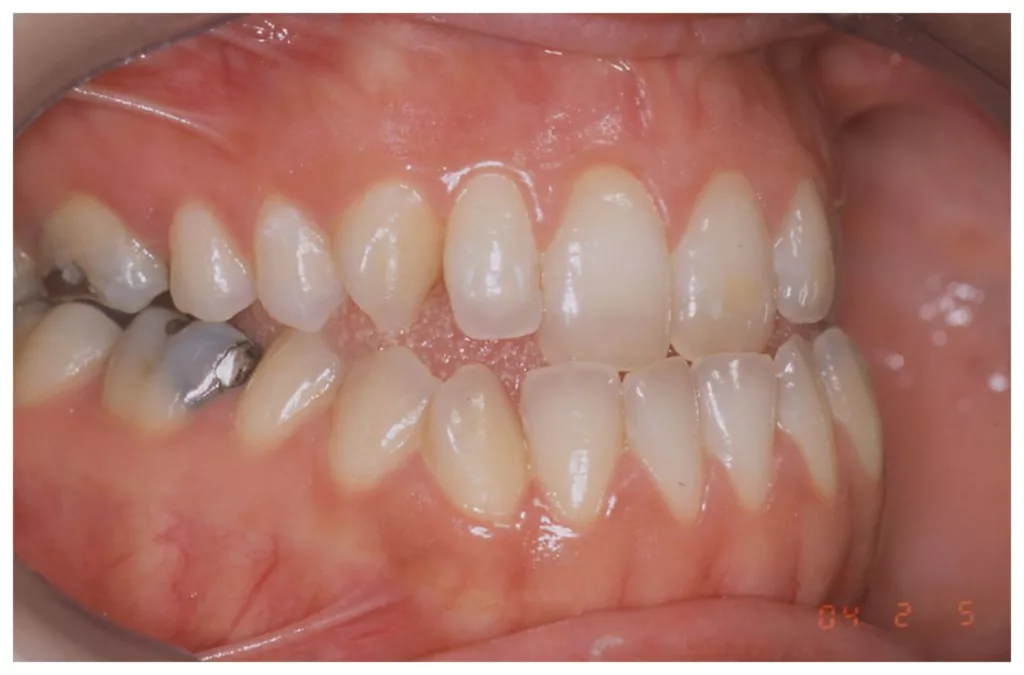

Les moyens thérapeutiques : L’orthodontie préchirurgicale

L’orthodontie pré-opératoire est destinée à corriger les désordres des arcades dentaires et à permettre au chirurgien d’obtenir au bloc opératoire une occlusion stable, équilibrée sans contacts prématurés c’est à dire sans interférences. Une occlusion stable sans interférences favorise une bonne consolidation osseuse. L’orthodontie est presque toujours réalisée avant la chirurgie.

Les mouvements orthodontiques les plus fréquemment réalisés par l’orthodontiste sont l’alignement, le nivellement et la coordination des arcades dentaires. L’objectif consiste à préparer un engrènement satisfaisant des dents au moment de la chirurgie.

La « décompensation» vise à annuler ou à diminuer les compensations subies par l’os alvéolaire en cas de malformation. Ces compensations peuvent être spontanées ; naturelles (« la nature » s’adapte pour diminuer les effets de la malformation sur l’occlusion) ou provoquées (un traitement orthodontique a été réalisé préalablement pour corriger ou diminuer le trouble de l’occlusion créé par la malformation).

En pratique, la décompensation alvéolaire orthodontique préchirugicale consiste à supprimer les compensations sur l’os alvéolaire avant l’intervention afin que le traitement chirurgical sur les bases osseuses soit aussi efficace que possible. Les décompensations pré-chirurgicales s’accompagnent souvent d’une aggravation de l’anomalie initiale de occlusion. Le patient en est informé.